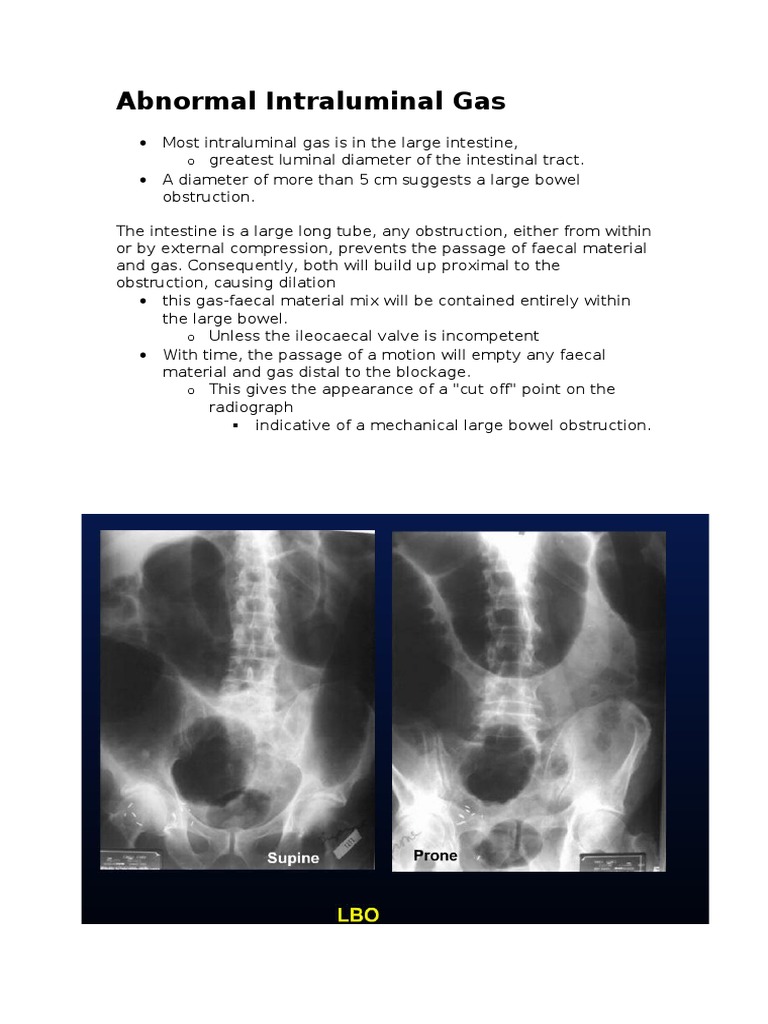

Abnormal Intraluminal Gas Gastrointestinal Tract Gastroenterology What Causes Gas In The Digestive Tract Too much gas in the digestive system can result in pain and other. There are various reasons why a person might experience gas. Reasons for gas in the stomach and upper abdomen include:. What causes gas in the digestive tract? Intestinal gas is a buildup of air in the digestive tract. Gas enters your digestive tract when you swallow air. What Causes Gas In The Digestive Tract.